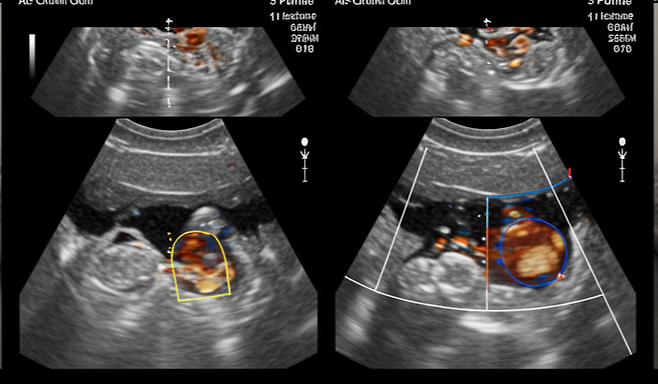

유방암은 완치율이 높은 암이지만, 발견이 늦으면 치료가 어려워질 수 있습니다. 정기적인 유방 자가검진과 전문의 검진, 유방촬영술(Mammogram)을 통한 조기 진단이 가장 중요한 예방책입니다.